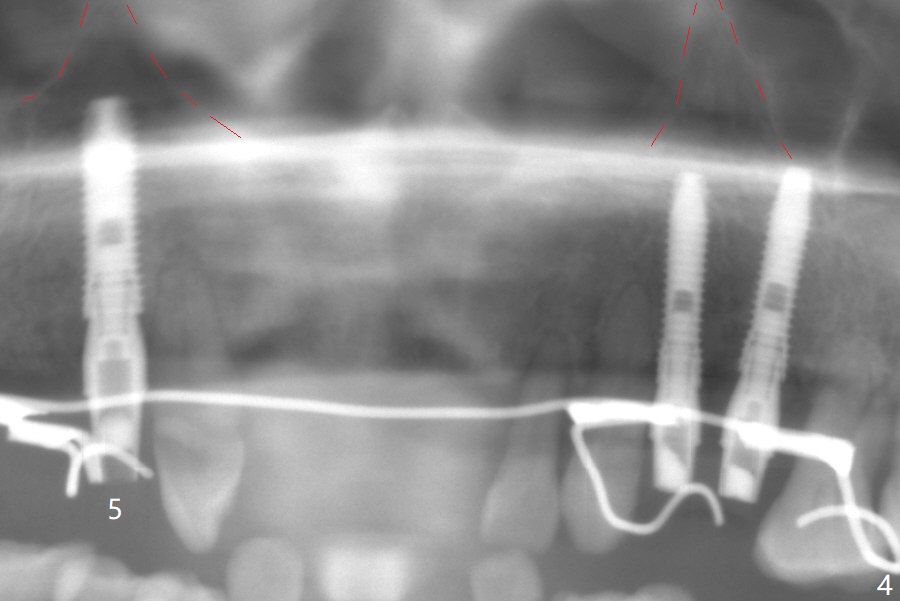

A 66-year-old woman returns to office requesting implant placement at #12 and 13 at an appointment supposed for #5 impression. Depth of osteotomy is 20 mm (gingival level, Fig.1 ( 2mm)). After correction of trajectory at #12 and 3 mm drill for 16 mm at the sites, two of 3.8x16 mm implant are placed with insertion torques of 35 and 15 Ncm, respectively (Fig.2). Before and after change into shorter abutments (4.5x4(4) and (5)), Vera Graft is placed (Fig.3 *). To increase stability, either increase the diameter (4 (Fig.4 at #5) or 4.5 mm instead of 3.8) or length of the implants (red dashed line: sinus floor). Or use dummy implants. The allograft appears to have been incorporated into the host bone nearly 4 months postop (Fig.5). The abutment of the isolate implant at #5 becomes loose twice (Fig.4). To reduce the chance of abutment loosening at #12 and 13, can you make splinted crowns? If the two separate crowns have been fabricated, can you make a slot (with light undercut) in the proximal area of each crown (Fig.6 (occlusal view): S) in addition to access hole (A)? After cementation, composite will be placed in the slots (lock) so that the crowns will not rotate and become loose.